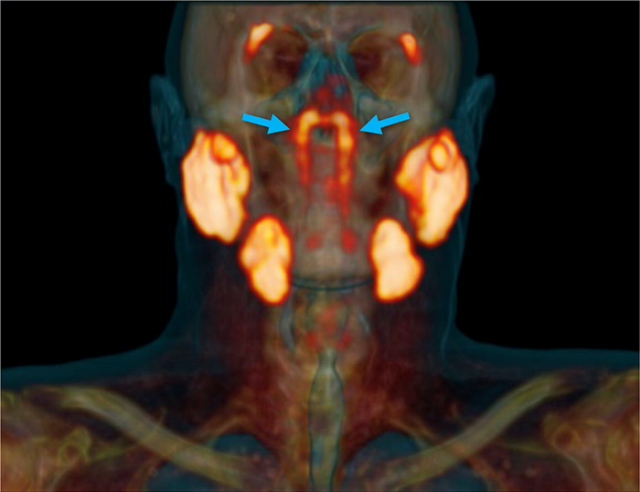

У задній частині носоглотки була помічена структура трубчастих залоз (на малюнку на них вказують сині стрілки) поруч з іншими основними слинними залозами (помаранчевого кольору).

Як пояснив онколог-радіолог Воутер Фогель з Нідерландського інституту раку, у людей є три набори великих слинних залоз, але не там, де їх знайшли.

Нове відкриття, зроблене командою Фогеля, набагато масштабніше і, схоже, вказує на наявність четвертого набору слинних залоз – розташованих за носом і над піднебінням, недалеко від центру голови людини.

Цей орган виявили на знімках усіх ста пацієнтів, які проходили обстеження, а також у двох трупів. «Наскільки нам відомо, ця структура не відповідала попереднім анатомічним описам», – пояснюють дослідники в своїй статті.